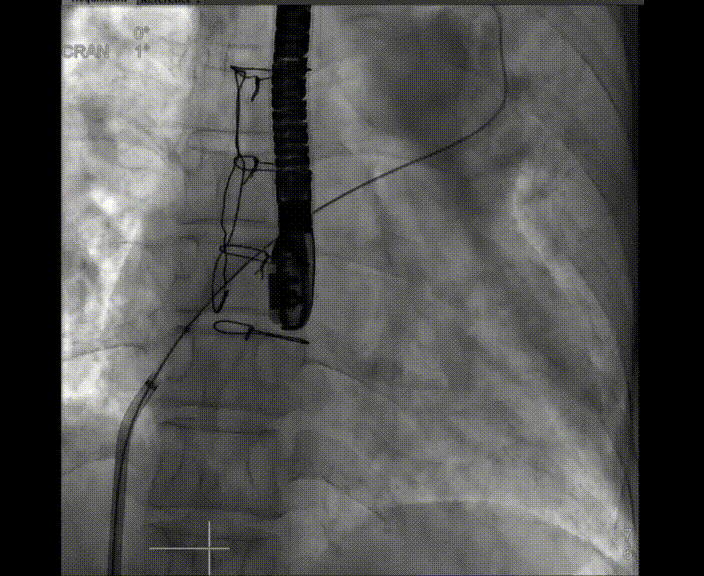

術中首先在局麻下穿刺股動脈、股靜脈,完成心導管檢查評估后轉為全麻,在食道超聲引導下穿刺房間隔,穿刺成功后將加硬導絲送入左上肺靜脈建立軌道,根據患者病情行球囊預擴張后植入6mm孔徑房間隔造孔支架,經透視及食道超聲評估支架左右盤展開良好,夾持于房間隔兩側,固定穩定、位置良好,食道彩超顯示房水平右向左為主分流,分流孔直徑符合預期大小,心導管檢查評估達到預期效果,釋放造孔支架。術后12h患者下床活動,恢復順利,擬于近日完善術后評估后出院。